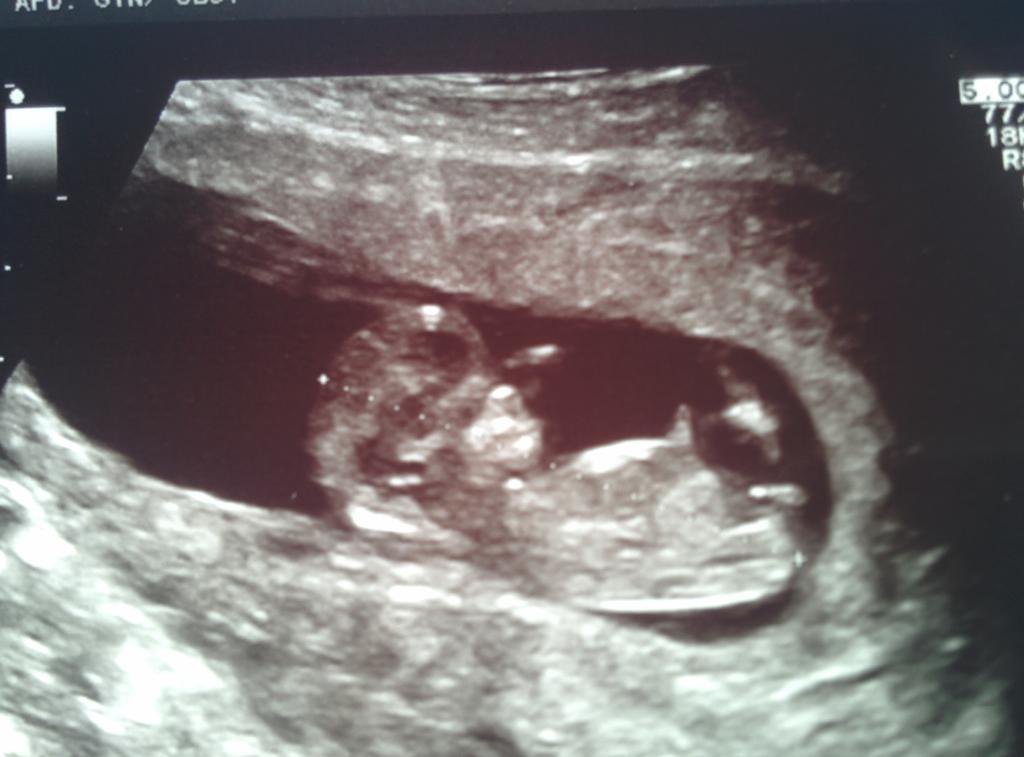

I have no clue if the nub is visible and where in my 11 week 4 day scan. Could anyone help me out? And if you see the nub, could you tell me where it is and whether it points to girl or boy? I would be very grateful for your help!

Attachment 23701Attachment 23702